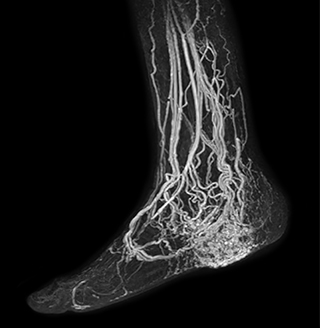

MRA of foot with 4D-TRAK XD

The images obtained with Ingenia Ambition show large coverage and high uniform signal. More vessels are visible than in a previous exam of the same patient on Achieva. The movies show a higher temporal resolution in the Ambition acquisition than in a previous Achieva 1.5T exam. Both exams use a FOV of 300 mm and voxel height and width of 0.78 mm.

4D Trak XD 1:54 min. TE 1ms, TR 3ms